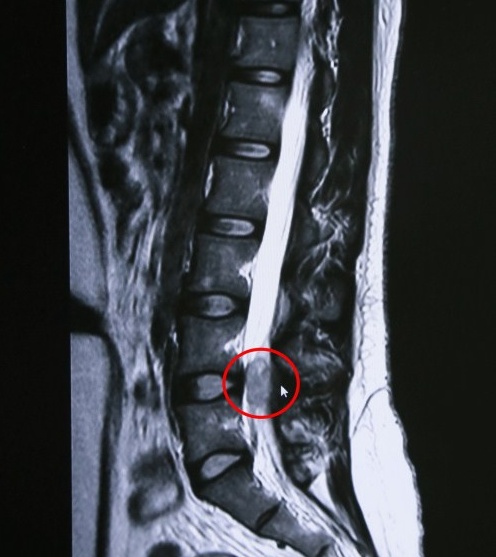

顾大叔长脊膜瘤的部位

家住虹口区的顾大叔,腰腿经常麻木、疼痛,特别晚上睡觉时疼痛得辗转难眠,去过多家大医院检查治疗,看过骨科、心内科甚至泌尿科,病情没有缓解反而加重,后来到蓝十字经核磁共振检查,孙海辉主任发现顾大叔L4/5椎间盘水平椎管点位,原来是脊髓内长了一个肿瘤!经过手术后,顾大叔康复出院。